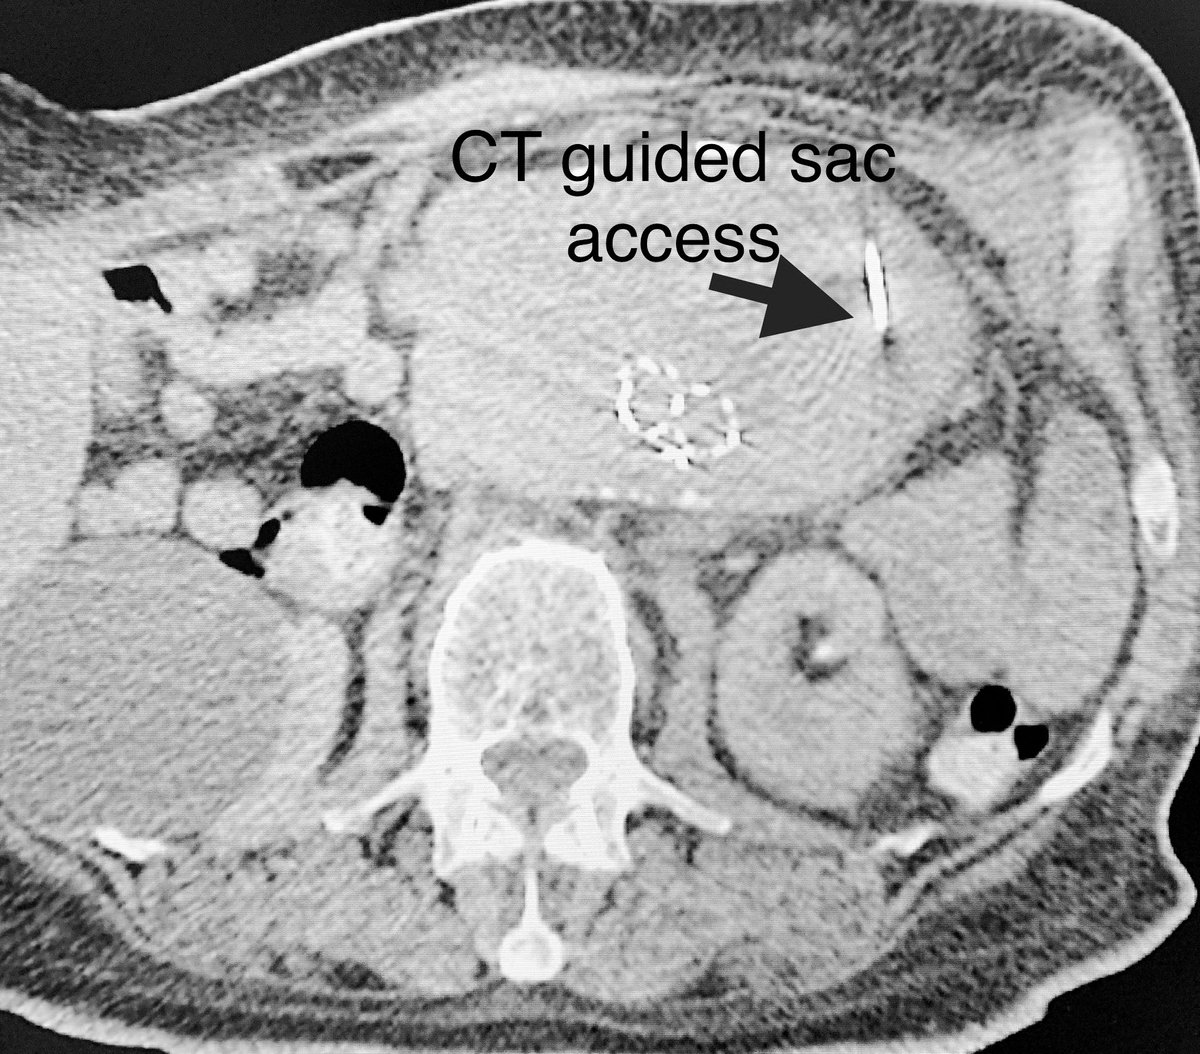

When conventional

#transarterial access to#endoleak type 2 fails,#CT guided#percutaneous direct#aneursym sac#puncture can be a#bailout.#embolization#irad#glue@SIRspecialists@SIR_ECS@SIRRFS@GESTSymposium#coils@PenVascular@VascularSVS@PairsWeb@AVIRnews#endograftpic.twitter.com/Rcgh4DpFMs